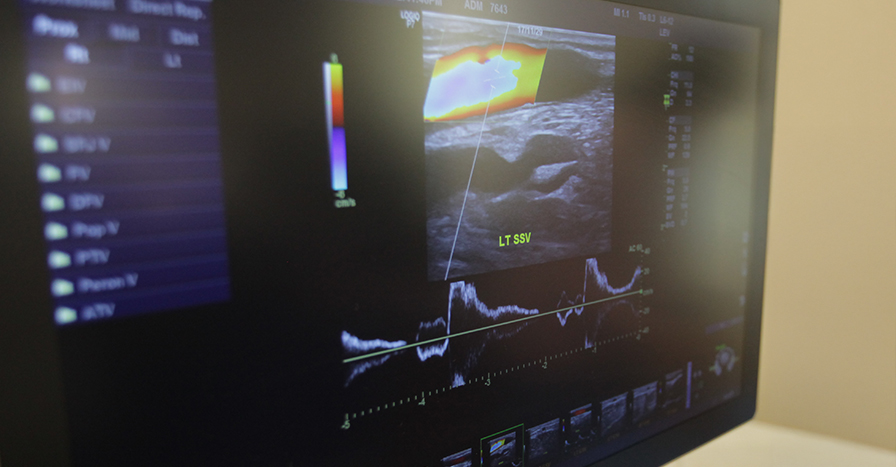

혈관 초음파 검사

혈관질환에서 가장 기초적인 검사로

혈관의 모양과 정확한 위치를 모니터를 통해 보여줍니다.

이를 통해 이상이 있는 부위를 정확하게 찾아내어

이에 맞는 적절한 치료법을 선택 할 수 있습니다.

특히 컬러 듀플렉스 초음파 검사는 역류가 있는 판막의 위치와 정도를

정확하게 보여주므로 하지정맥류를 진단에 필수적인 검사방법 입니다.

혈관초음파검사장비가 과거에 비해 현격히 좋아져

불필요한 방사선 노출이 되는 혈관조영술이나 CT 검사는

필수적으로 할 필요는 없습니다.